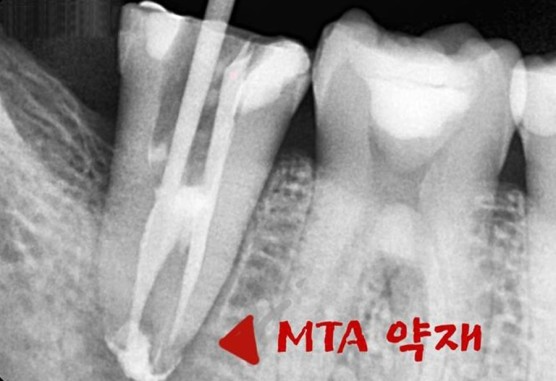

[MTA 약재를 이용하여 신경치료 마무리]

치아는 신경치료가 제일 어렵다는 C형 모양을 가지고 있었습니다.

여러번의 소독을 거치자 치아의 동요도도 좋아지고 증상도 완화되어

MTA 약재를 이용해서 신경치료를 마무리 하였습니다.